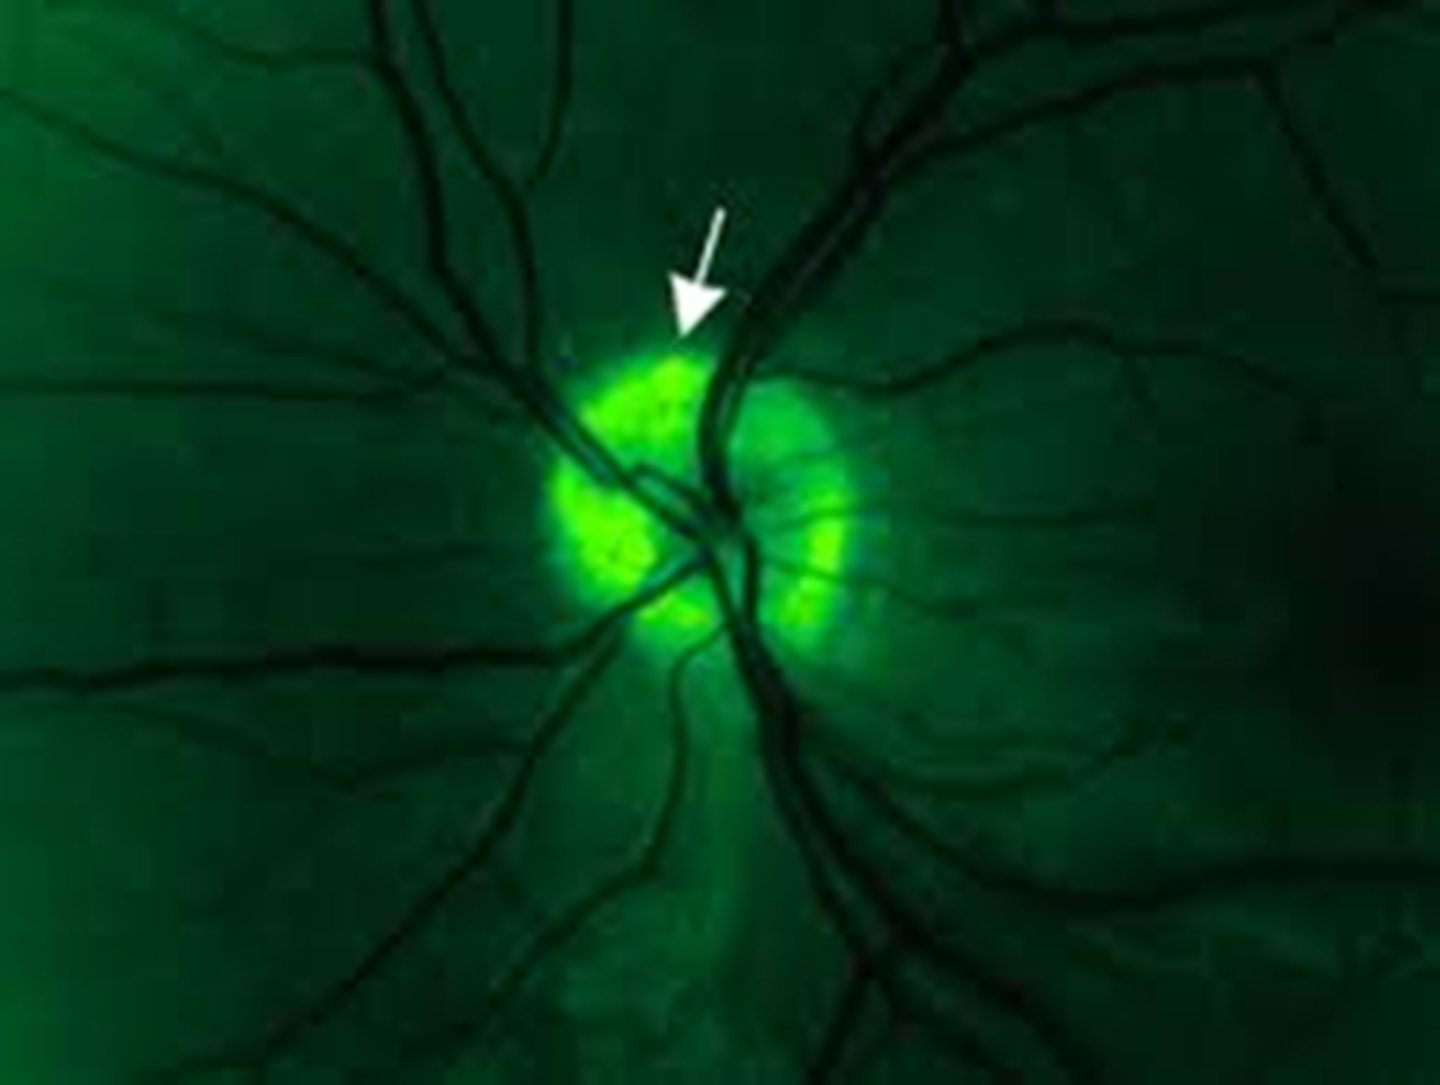

How do disc drusen appear on FAF?

hyperAF drusen within the hypoAF nerve head

How do surface drusen appear on early IVFA?

blockage

How do surface drusen appear on late IVFA?

nodular staining

How do buried drusen appear on early IVFA?

no staining or nodular staining

How do buried drusen appear on late IVFA?

late peripapillary staining (noduler, circumferential)

How does disc edema appear on IVFA?

early and late diffuse leakage

How does co-existent drusen and edema appear on IVFA?

early = edema leaks, drusen stain

late = edema leaks, drusen stain